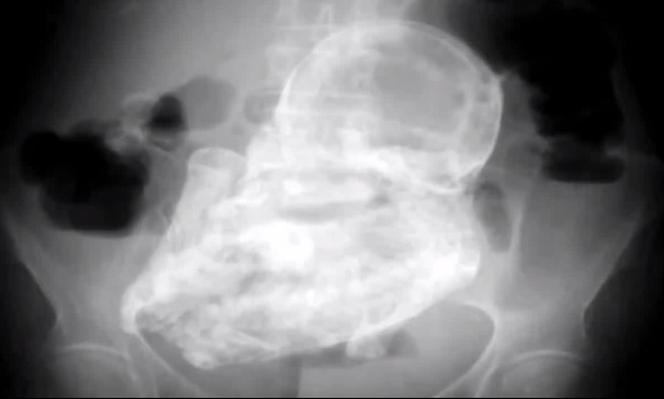

Skamieniałe dziecko w łonie 84-letniej staruszki. Martwy płód był tam 44 lata!